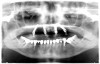

Utilizing two axially orientated implants in the anterior region and two tilted posterior implants (Figure 1), the All-on-4 concept facilitates an avoidance of anatomical structures as well as the accurate placement of longer implants into better quality bone anteriorly. The tilted posterior implants are key components of this concept. In the mandible, tilted posterior implants facilitate excellent bone anchorage without interfering with the mental foramina. In the resorbed posterior maxilla, the tilted implants are an alternative to sinus floor augmentation.

Fig 1. A radiograph of the All-on-4 concept

depicting two axially orientated implants in the

anterior and two tilted implants in the posterior.

Figure 1